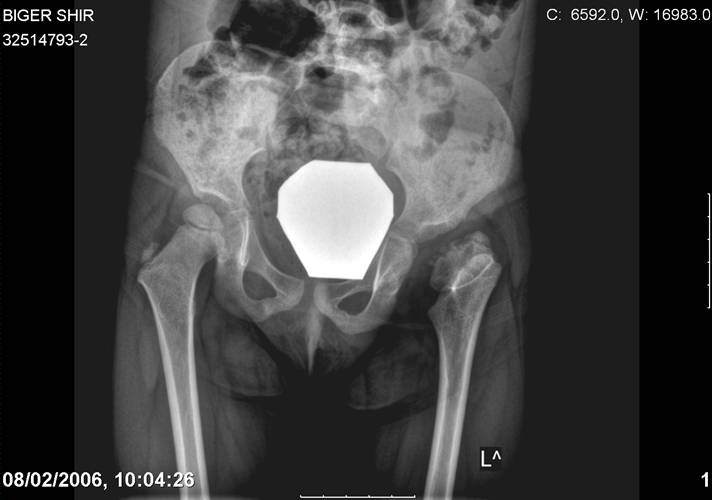

Здравствуйте, уважаемые коллеги.Обратилась девочка 6-ти лет из жалобами на боль в левом т/б суставе,хромоту Из анамнеза : ребенок лечился с рождения по поводу врожденного вывиха бедер. В возрасте 3- х лет в одной из клиник была выполнена остеотомия таза по Пембертону и варизирующая остеотомия бедра слева, справа - остеотомия таза по Солтеру и остеотомия бедра. Посоветуйте тактику лечения. С уважением Ihor

Smotritsya parshivo konechno(pseudoacetabulum,partial AVN), no v6 let ya by popytalsya ispravit chto moghno:shortening (ne boyatsya ubrat bolshoi fragment),derotation(30 gradusov ne bolshe)+pelvic osteotomy in true acetabuluam area.Obyazatelno takghe open reduction with wide capsular exposure.

Navernoe Dega

Chto by ne byt goloslovnym posilau vam svoi sluchai gde sdelal vse chto napisal vyshe

Уважаемой Ihor! Следует дообследовать ребенка, проведя РКТ или МРТ. Необходимо установить взаимоотношение головки бедренной кости и вертлужной впадины слева, оценить угол антеторсии и истинный ШДУ. Далее решать вопрос об оперативном лечении. Скорее всего показана деторсионно-варизирующая остеотомия в межвертельной области левого бедра и остеотомия таза типа Солтера (хотя ацетабулярный индекс великоват, т.е. более 30-35 градусов). Справа следует понаблюдать и периодически проводить курсы ФТО и ЛФК. Если Вы не имеете опыта реконструктивной хирургии ТБС у детей, то лучше отправить пациента к детским ортопедам. АИФ